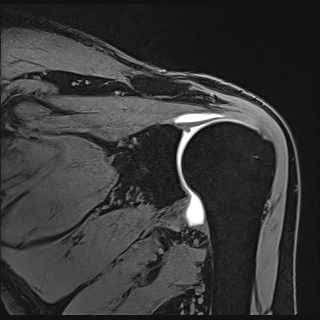

IRM de l’épaule

La plupart des demandes d’IRM sont d’origine post-traumatique. L’articulation de l’épaule ou gléno-humérale est une articulation à grande amplitude, la coiffe des rotateurs est composée de quatre muscles principaux : le muscle supra-épineux, le muscle infra-épineux, le muscle sous-scapulaire, le muscle teres minor.

Lorsqu’une perte de mobilité de l’épaule est découverte souvent post traumatique, plusieurs lésions sont suspectées : une déchirure du tendon de l’un de ces muscle, une inflammation d’un de ces tendons (tendinopathie), une lésion du bourrelet (labrum) permettant un contact encore l’omoplate (scapula) et la tête de l’humérus. Une fracture peut aussi être déterminée ou une lésion du tendon du long chef du biceps passant aussi à ce niveau.

La plupart de ces lésions peuvent être détectables soit par échographie de l’épaule soit par IRM, l’IRM restant le plus précis dans tous les cas.